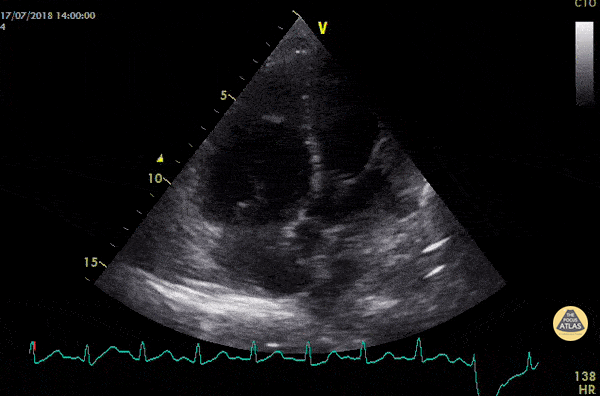

akute-rv-belastung